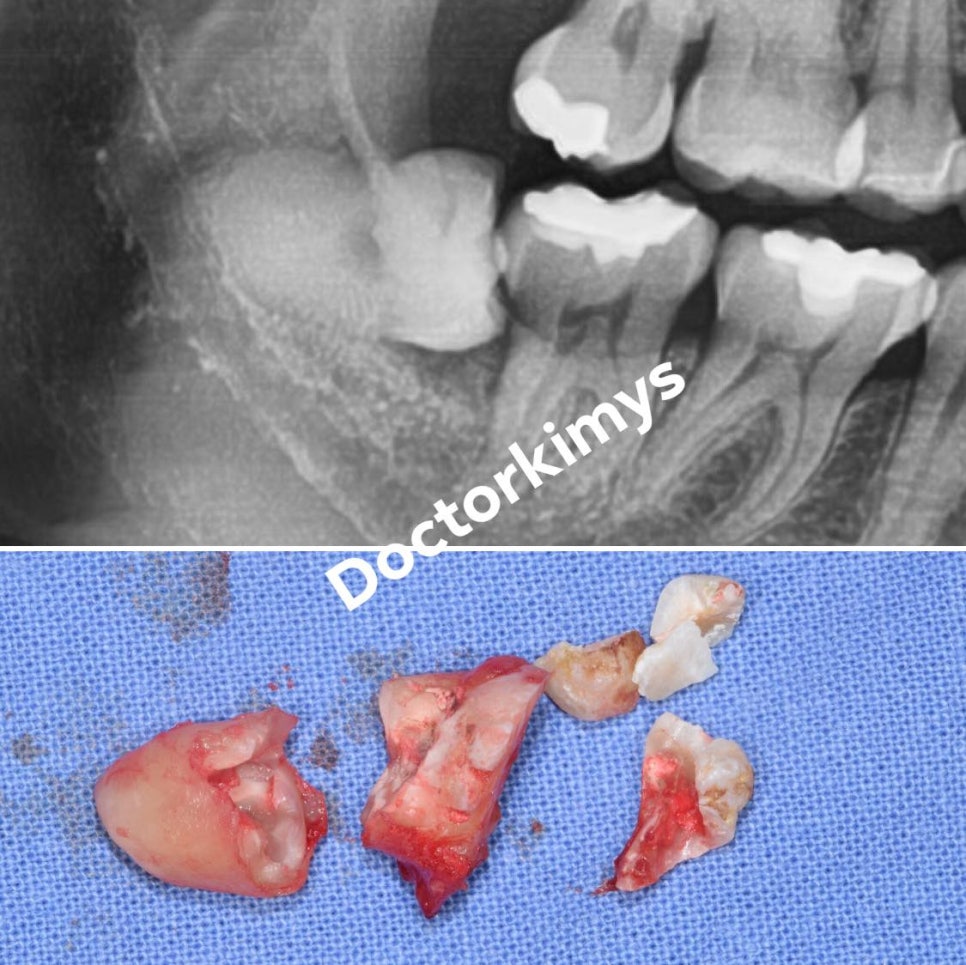

저희 원장님의 케이스를 보여드려볼께요.

기울어져 있거나 매복 된 제3대구치를 뽑을 땐 많은 분들이

치아도 쪼개고, 뼈도 깎아낸다는 생각을 많이 하십니다.

이 사례는 저희 원장님께서 치조골 삭제 없이 오로지 치아만 쪼개어 발거를 한 경우랍니다.

이렇게 뽑고 나면 왠만한 분들은 통증과 붓기가 없어

다음날 소독을 하러 오실 때 굉장히 편안해 하는 모습을 볼 수 있어요.

당장 이를 뽑는 것만 열심히 하는 것이 아니라

다음날 붓기와 통증까지 고려하니까 사랑니 발치 전문 맞죠!?^^